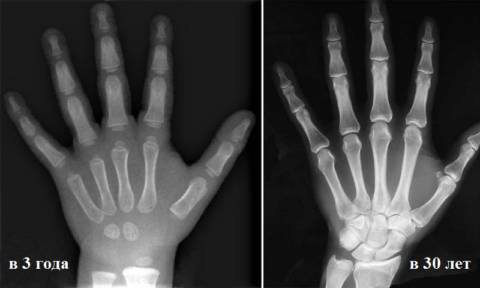

Кстати, лучевая диагностика костносуставной системы, а именно рентген или компьютерная томография ЛЗС применяется в педиатрии и судебно-медицинской практике для определения биологического возраста.

Это возможно до 23 лет у мужчин и 21 года у женщин. Выводы делаются на основании исследования ядер окостенения в костях запястья и в оконечностях лучевой и локтевой кости в ЛЗС, наличия синостозов хрящевой ткани с костной.